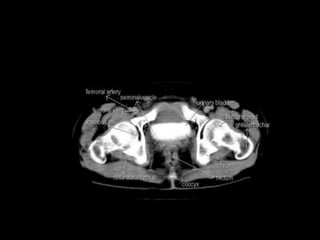

Cross section anatomy of abdominal ct scan

Cross section anatomyof abdominal ct scan